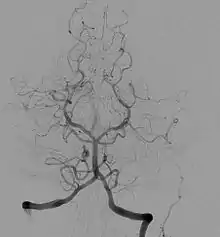

Angiografi af blodårerne i hjernen.